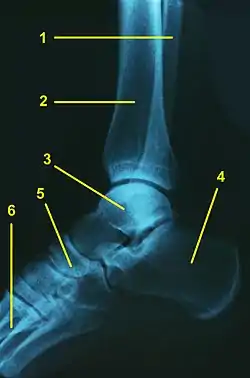

![]() Radiografía lateral de un tobillo normal: 1.Peroné, 2.Tibia, 3.Astrágalo, 4.Calcaneo, 5.Escafoides, 6.Metatarsianos | ||